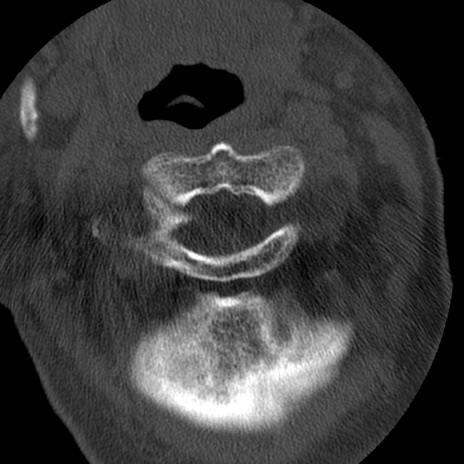

症例50 頚椎CT(横断像)

異常所見と診断は?

頚椎CT

冠状断像